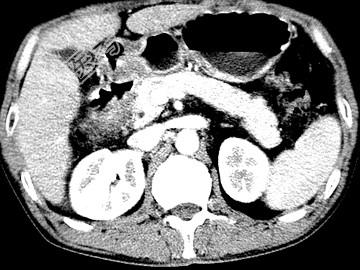

- 单项选择题女,63岁, 右上腹疼痛,呈不规律性钝痛, 伴恶心,时有呕吐, 呕吐物为胃内容物混有胆汁,CT检查如图, 最可能的诊断是 ( )

A、十二指肠克罗恩病

B、十二指肠结核

C、十二指肠癌

D、十二指肠淋巴瘤

E、十二指肠平滑肌瘤